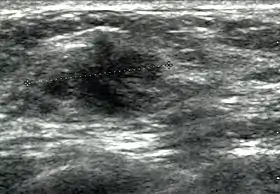

Cancer ultrasound image | |